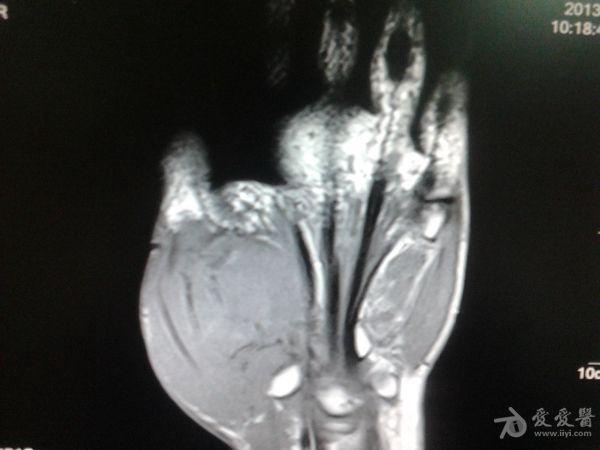

右第一掌骨、大多角骨肿瘤

男性患者,81岁,右手肿痛3个多月。无任何其它症状。体查:右手第一掌骨部肿胀明显,第一指活动受限,余四指活动可,腕关节活动小部分受限,活动时会痛。影像学检查如下。活检示:弥漫性大B细胞淋巴瘤。大家看看需不需要截肢?现在有人主张手术;有人主张不手术,直接化疗。大家有什么看法?